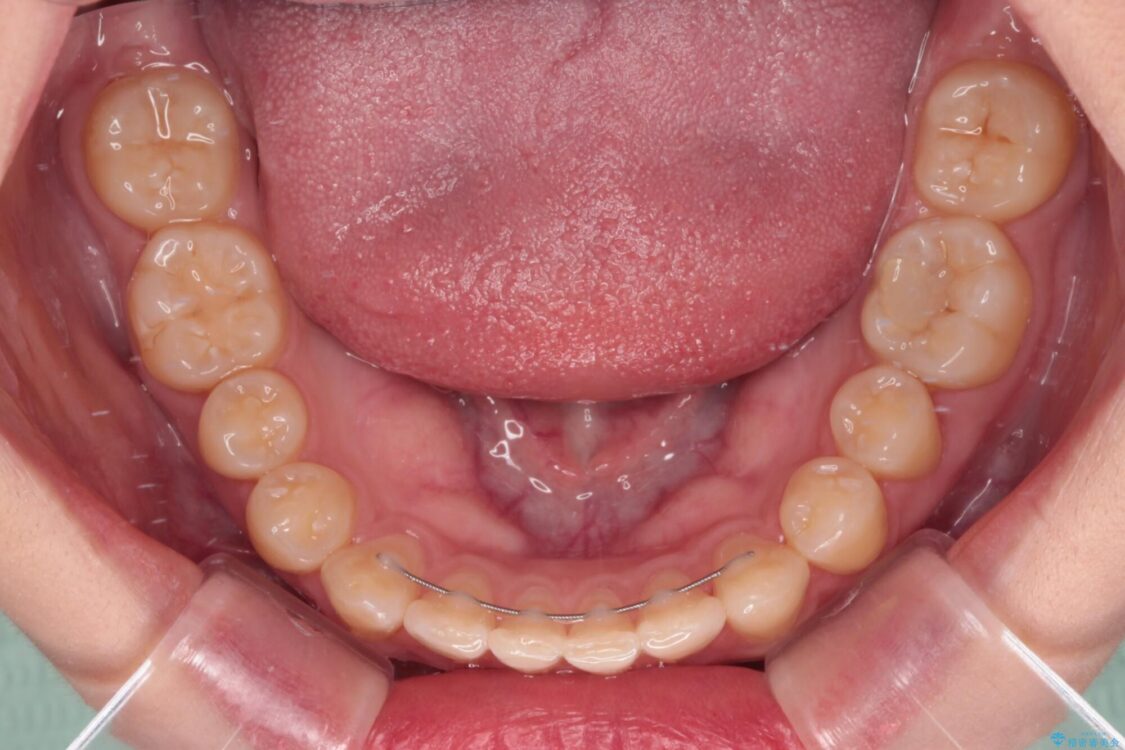

治療前

• 治療途中の奥歯と矯正治療の後戻り インビザライン・ライトによる矯正治療 治療前画像